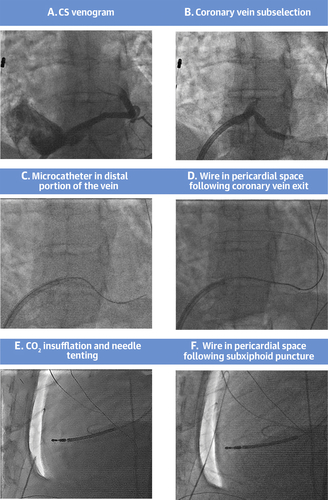

Very interesting data! Keep a eye out for editorial with @akillumd discussing this innovative paper. An opportunity to improve safety. @shivkumarmd

What are the barriers to doing this in all labs, if ZERO RV punctures? Would love to hear your thoughts👇 New Era in Epicardial Access for the Ablation of Ventricular Arrhythmias: The Epi-Co2 Registry https://t.co/kWqnord2wR